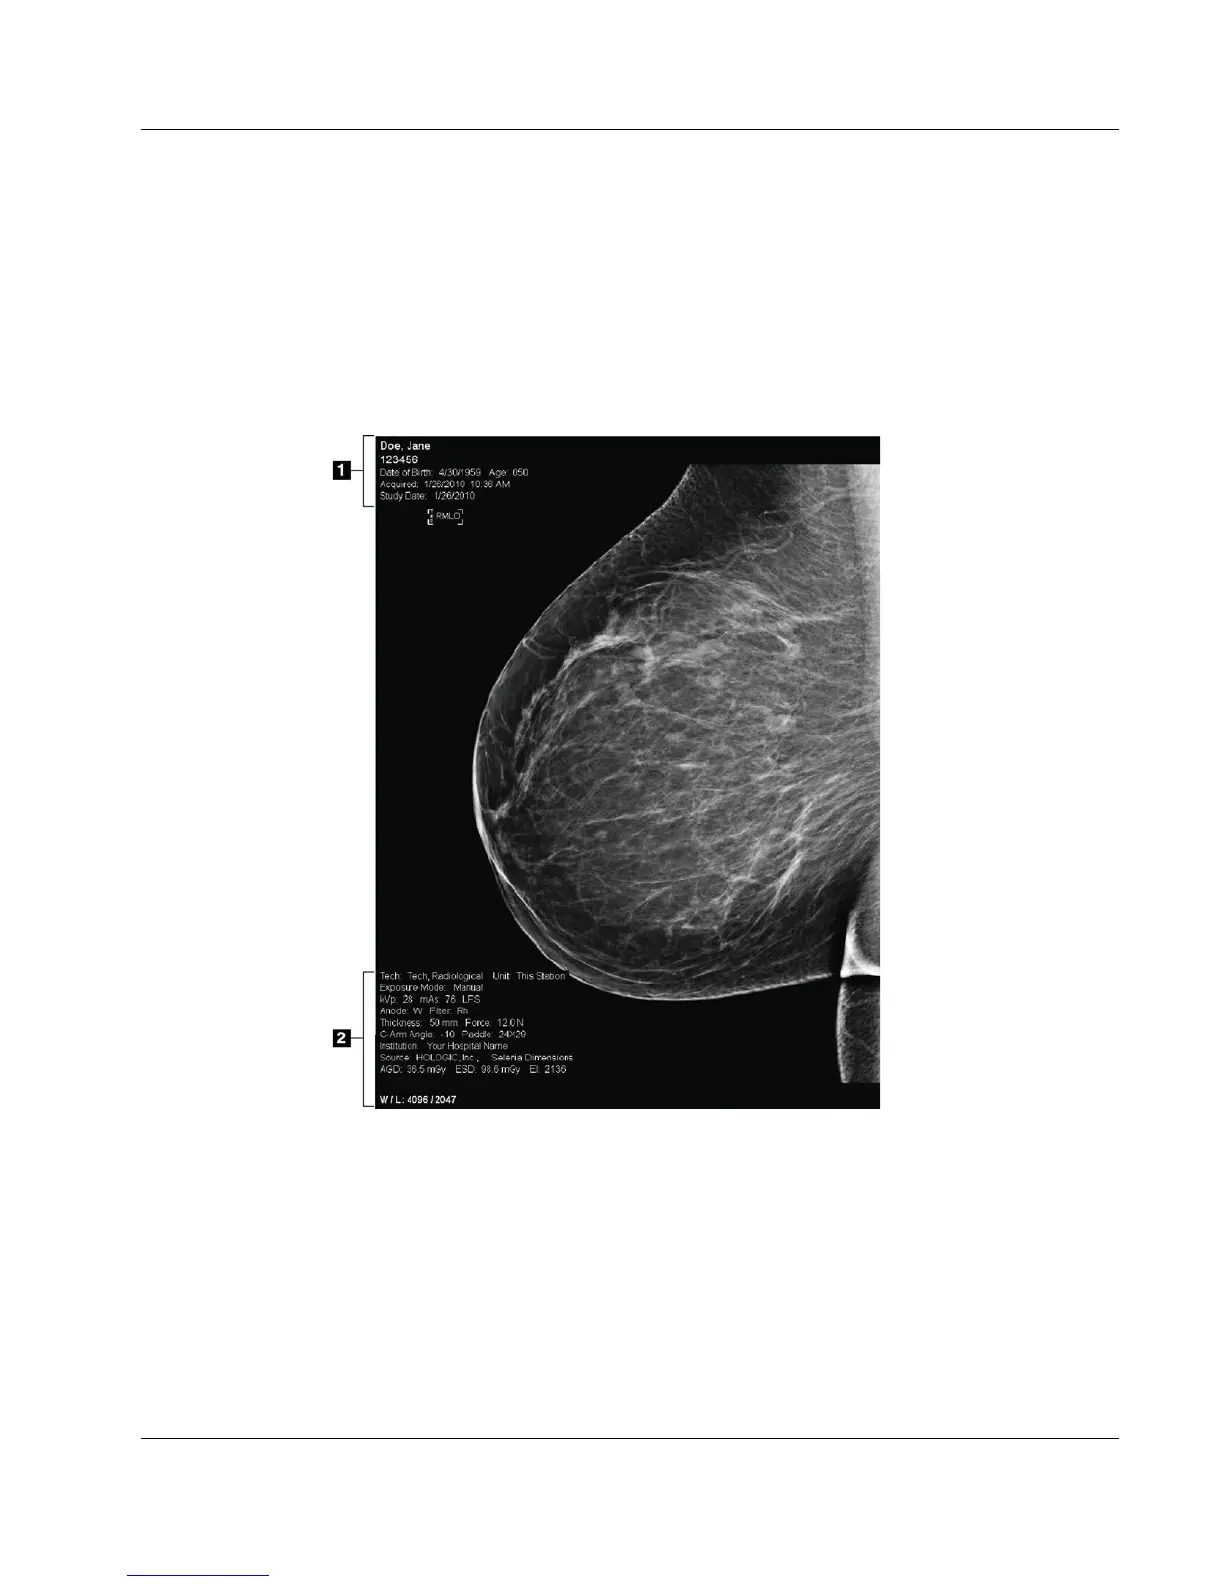

Figure 40: Image Display Screen

Figure Legend

1. Patient information and exam date

2. Exposure information, including:

x Exposure techniques

x Patient dose

x C-arm angle

x Compression thickness and force

x Facility and technologist information

After you make an exposure, the acquired image opens on the Image Display monitor.

Patient and procedure information can be displayed on the screen. To turn the

information on or off, go to the Tools tab in the Procedure screen and select the Patient

Information button.